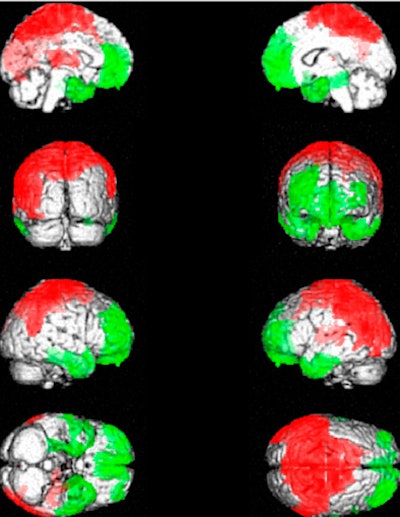

| The images show the anatomical localization of peak significant differences between brain SPECT of patients with fibromyalgia and healthy subjects. Patients with fibromyalgia exhibited posterior hyperperfusion (red), including of the somatosensory cortex, and hypoperfusion (green) of frontal, cingulate, temporal, and cerebellar cortices. Images courtesy of the Journal of Nuclear Medicine. |

Compared with healthy controls, patients with fibromyalgia exhibited posterior hyperperfusion, including of the somatosensory cortex, and hypoperfusion of the frontal, cingulate, temporal, and cerebellar cortices in particular, the temporal hypoperfusion including the polar and mediobasal cortices.